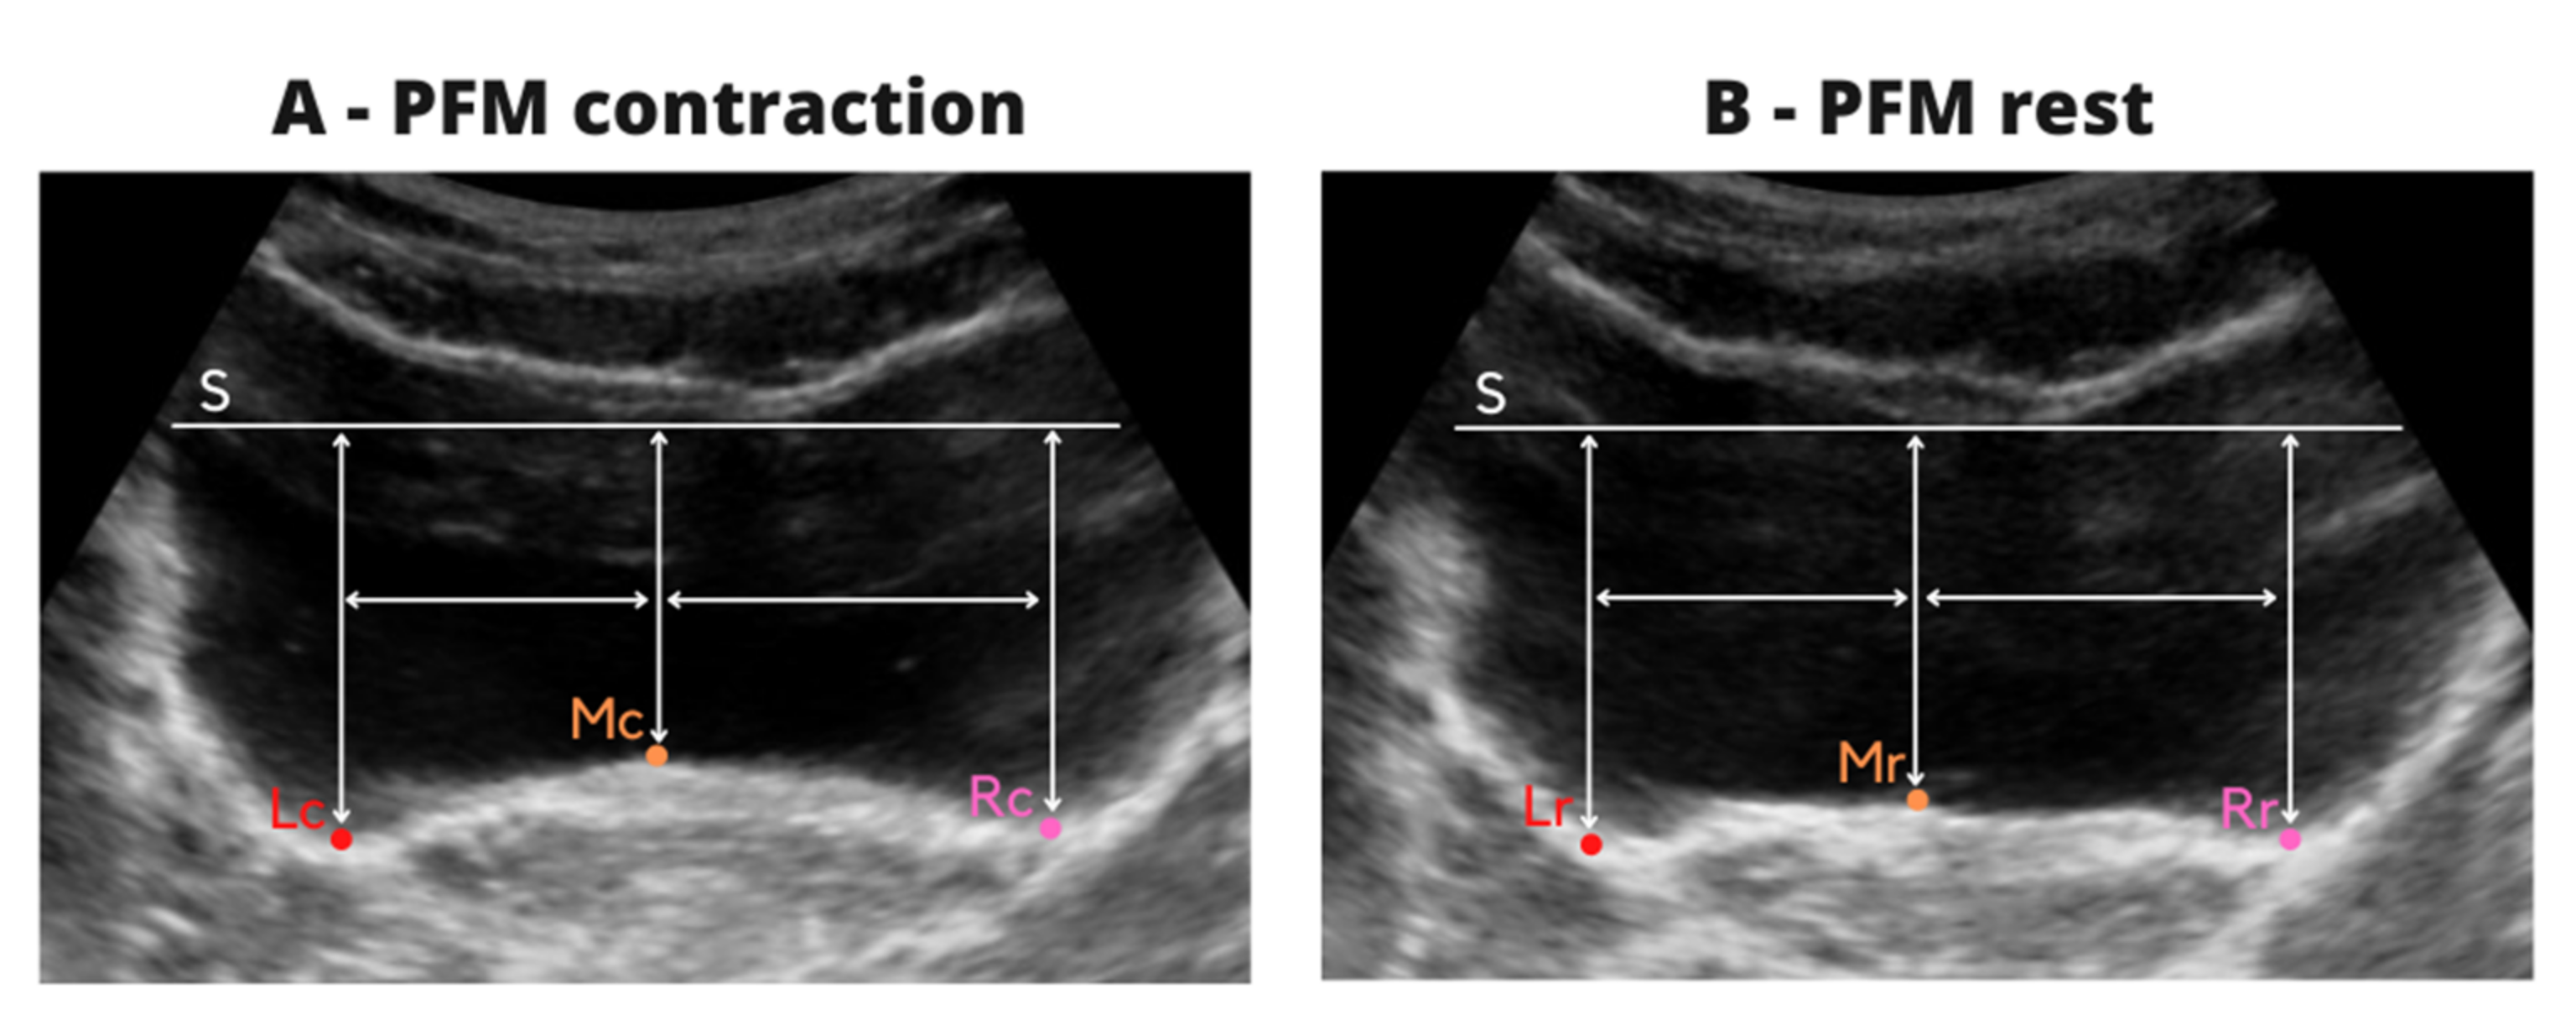

- horizontal tangent (S) and the highest point at the middle of the bladder base (MC),

- horizontal tangent (S) and the lowest point of the bladder base to the left (LC) and right (RC) of the MC point,

- the distance between the MC to LC and MC to RC points was measured and then, the mean value from two images was calculated. This procedure allowed marking of the three points on the bladder base on resting images at the same location, and to calculate the reliability of resting evaluation at the same points as the reliability of contraction.

- horizontal tangent (S) and the highest point at the middle of the bladder base (MR),

- horizontal tangent (S) and the LR point—located at the base of the bladder to the left of the MR point corresponding to the distance between the points MC–LC on the images from contraction,

- horizontal tangent (S) and the RR point—located at the base of the bladder to the right of the MR point corresponding to the distance between the points MC –RC on the images from contraction.